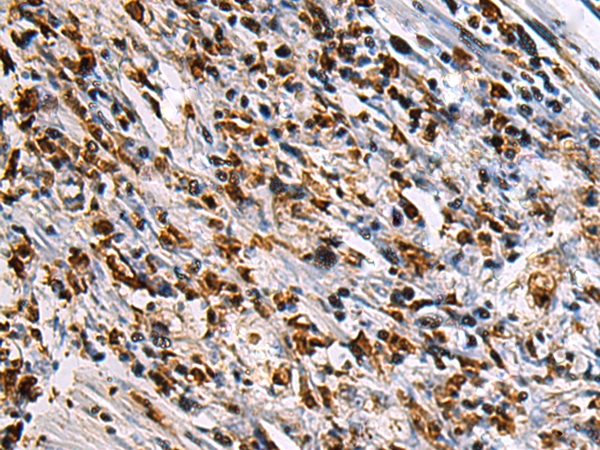

IHC positive control:

IHC Recommend dilution:

100-300